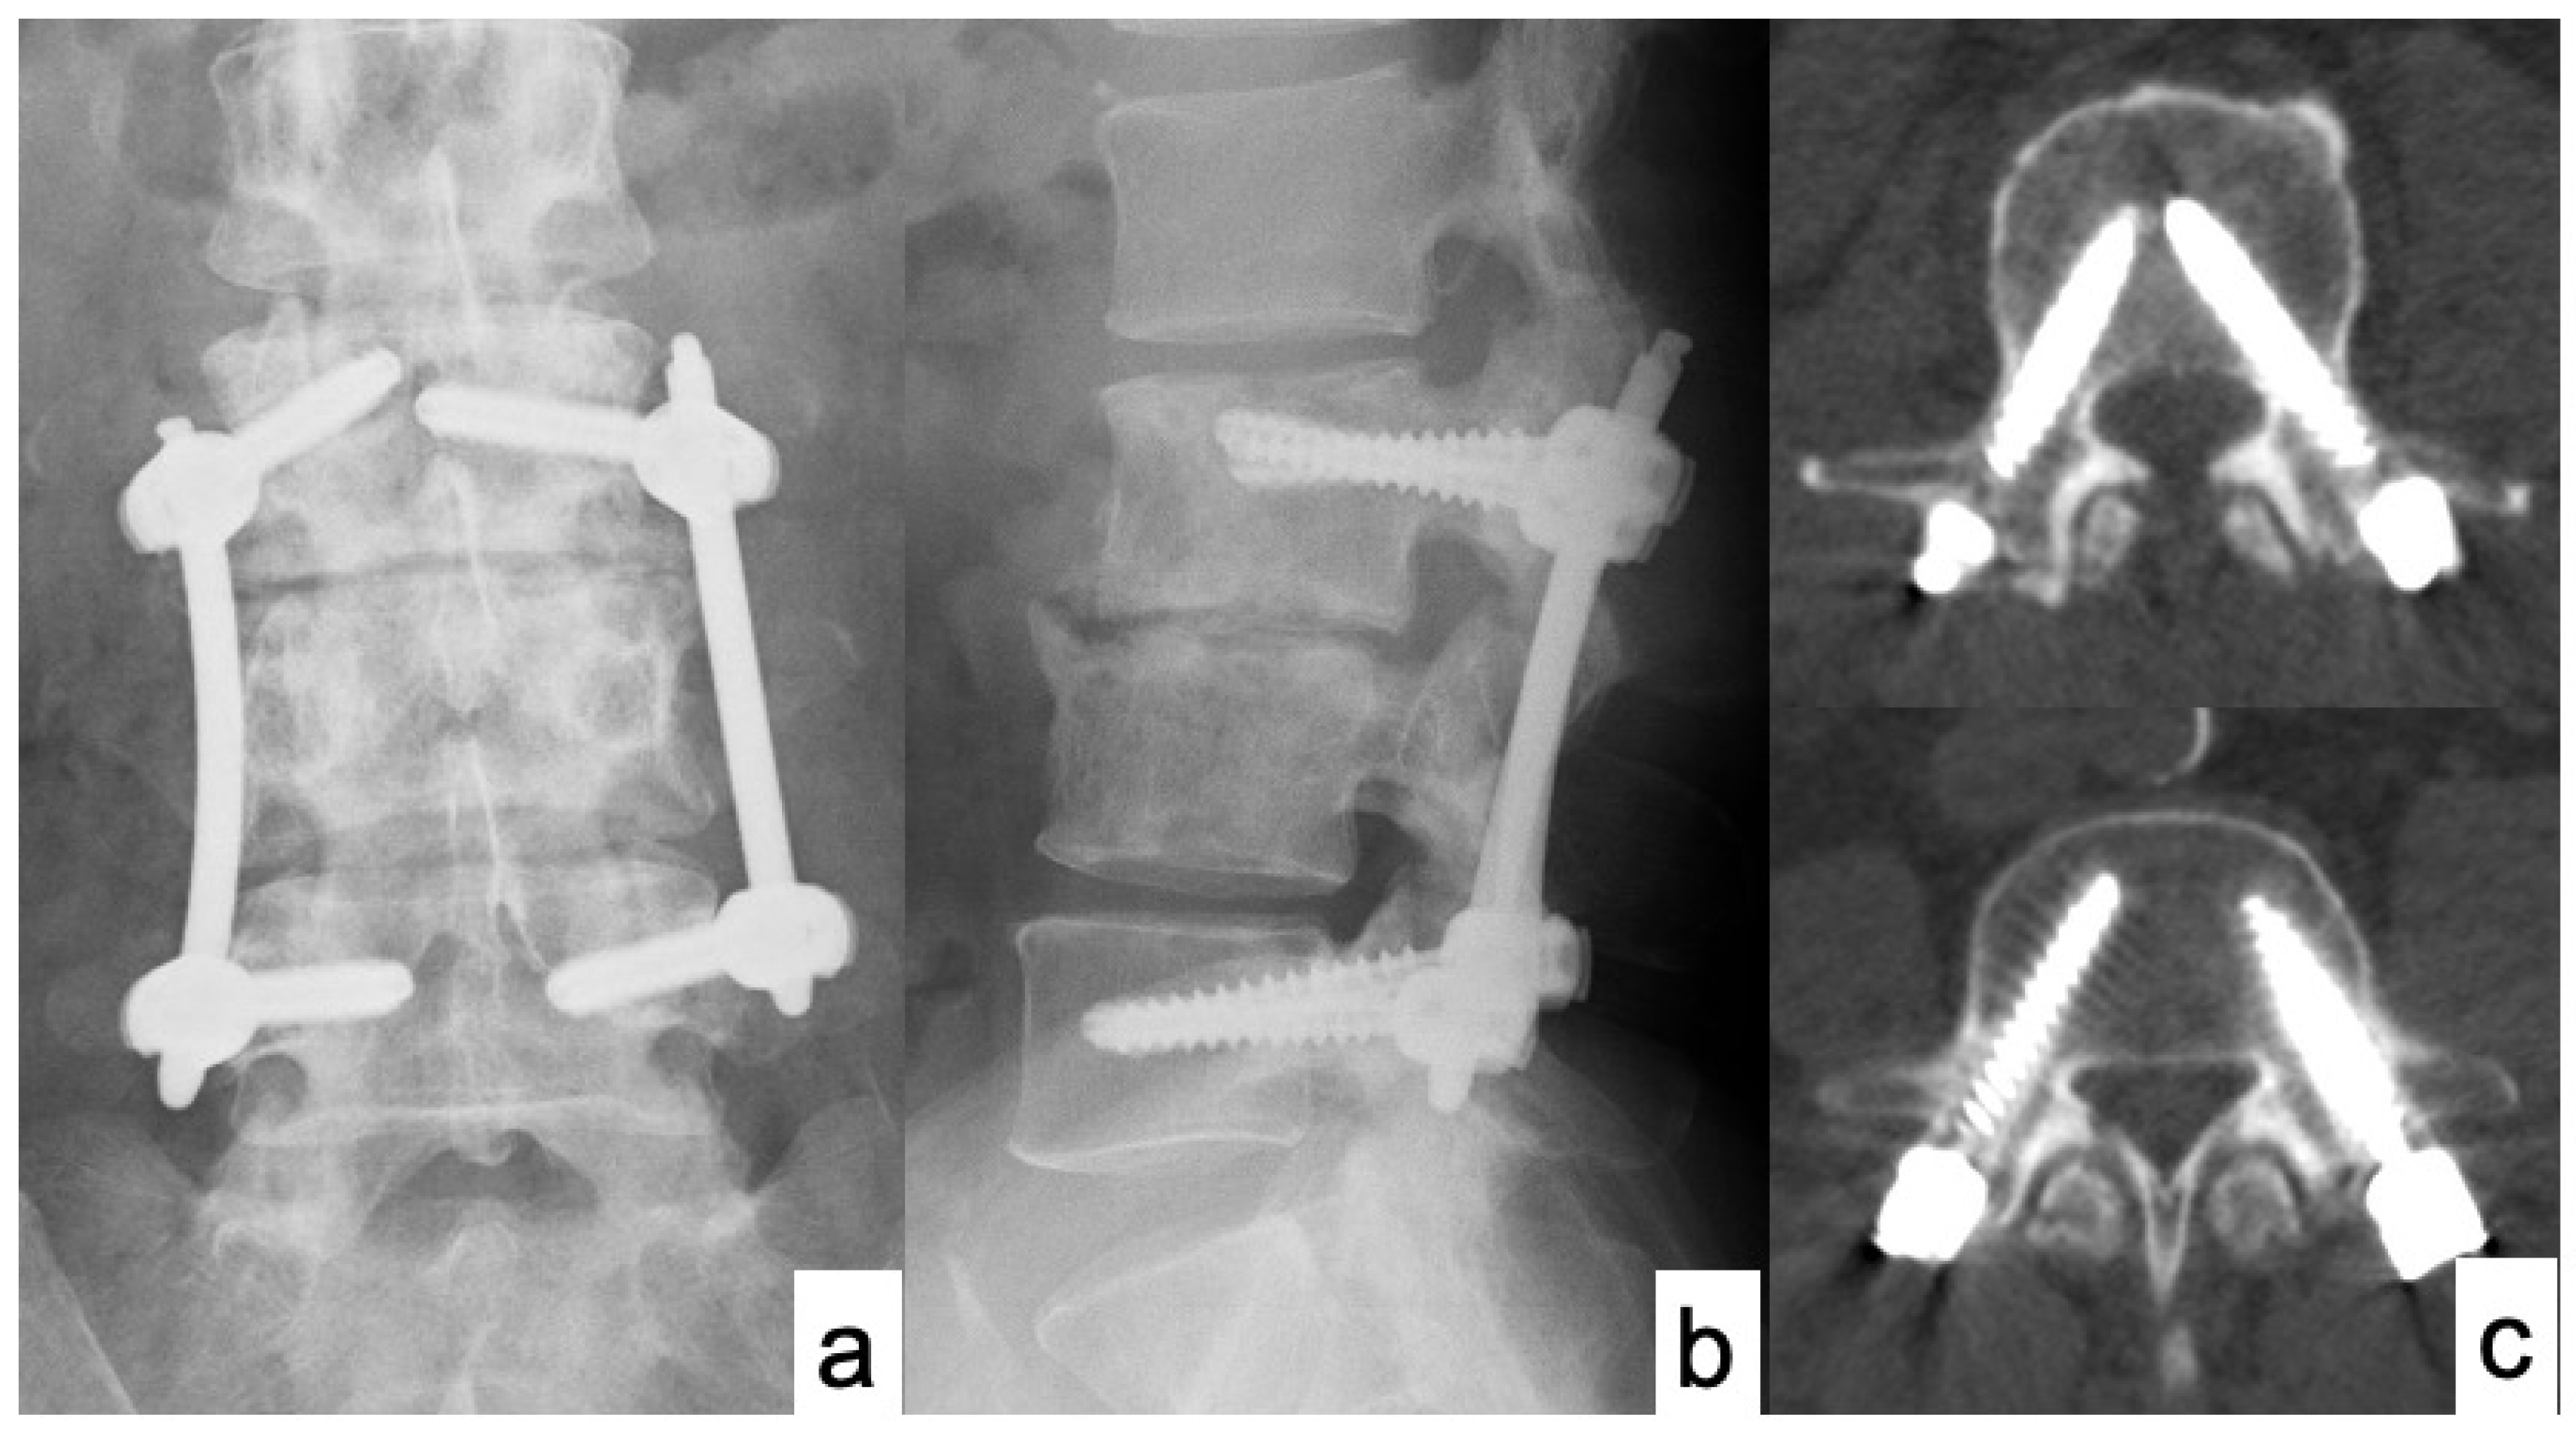

Case